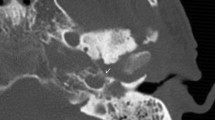

Computerized tomography (CT) is the most commonly used imaging modality for diagnosis and follow-up by ENT clinicians for skull base osteomyelitis [16]. CT imaging is often viewed as a relatively easy and fast method to acquire an overview of the mastoid region. The strength of this modality is the evaluation of bone erosion and demineralization, especially with the use of (ultra)thin high-resolution CT in multiple planes [Fig. 3(2a)]. Skull base osteomyelitis is often caused by malignant otitis externa (MOE), although some cases have been described starting from the paranasal sinus due to acute-on-chronic sinusitis [9•]. Typical findings due to MOE is swelling of the external ear canal near the fissures of Santorini during physical examination [9•] (Fig. 4). CT imaging during this early stage will thus be non-specific as it shows soft tissue swelling with thinning of the fat planes (Fig. 4b). Detection of subtle changes can be improved by comparing the affected side with the contralateral one, although one must be careful to miss bilateral SBO cases. The spread for the external canal to the anterior wall (and thus posterior wall of the temporal mandibular joint) will show erosive changes of osseous structures. It is important to take note that skull base osteomyelitis does not always show osseous destruction in an early stage. The destruction of bone by itself is relatively a late phenomenon and in case of angioinvasion (fungal infections) changes in bone structure occur even later [17].

Abscess formation and involvement of facial nerve. A 65-year-old male with a history of a kidney transplant presented with headache and cranial nerve deficit, with dysphonia and facial nerve palsy. Otoscopy revealed a red and painful EAC. At MRI, there is SBO involvement of the bone marrow of the temporal bone and the clivus, with medial spreading pattern of the soft tissues (image 1a arrows). There is a hypointensity of the subtemporal soft tissues with obliteration of normal fatplanes in the masticator space. At DWI, a slight hyperintensity is shown (image 1b arrow), with relative low ADC (image 1c). At high-resolution CT demineralization and cortical destruction of the skull base and clivus can be appreciated (image 2a arrows). Follow-up PET-MRI (image 3a T1-w, 3b CE-T1-w) 1 month later shows SBO with expansion over the midline (crossed pattern) and abscess formation bilateral at the prevertebral region (image 3b arrowheads), with intense FDG avidity (image 3c PET, 3d colour fused PET-MR image). Involvement of the VII cranial nerve was seen at contrast-enhanced T1-w imaging, without osseous destruction of the facial canal (image 2b detail of skull base on T1-w-fs, arrow indicates enhancing facial nerve) (Color figure online)

HRCT widening of temporomandibular joint. A 67-year-old male presented after 5 weeks with signs of external otitis and pain during chewing, without improvement after admission of topical antibiotics. An EAC polyp was removed. Bacterial culture revealed Pseudomonas aeruginosa. A non-contrast HRCT of the temporal bone was performed. The figure shows a bone window (image a) and soft tissue window (image b). Non-contrast-enhanced CT shows thickening of soft tissue of the EAC (image b arrow) as well as an anteriorly displacement of the mandible head with widening of the temporomandibular joint (black double arrow), indicating anterior spread of inflammation to the TMJ. At this point, no signs of bone erosion were present. Symptoms resolved after 4 weeks of iv. antibiotic therapy

The most frequent direction of SBO (80%) is expansion through the temporal bone with destruction of the temporomandibular joint, and erosion of the clivus [2••, 6, 18] [Fig. 5(2c, d)]. Involvement of the middle ear warrants malignancy as differential diagnosis, but can be present in SBO. The skull base foramina should be checked for irregularity and demineralization. The jugular foramen, the stylomastoid foramen, the lacerum foramen are frequently involved.

Transverse sinus thrombosis. A 76-year-old female presented with pain and otorrhea of the left ear since 2 months, with hearing loss and tinnitus. The symptoms were accompanied by a left-sided headache. No cranial nerve deficit was present. No history of diabetes or immune suppressive disease was present. Culture from the EAC revealed Pseudomonas as causal agent. An MRI was made at presentation with T2-w (image 1a) and T1-w (image 1b) series. At T2-w (image 1a) high signal intensity is present in the mastoid air cells at the left side (straight arrow), with loss of flow voids of the sigmoid sinus (arrowheads) indicative for sinus thrombosis. T1-w images show loss of signal intensity of the bone marrow of the skull base (image 1b, bent arrow), consistent with SBO. FDG-PET-CT performed 3 weeks after initial diagnosis confirms the location of SBO with increased uptake at the left temporal bone and surrounding soft tissue (image 2a, 2b fused PET-CT image, thin arrow). On the diagnostic CT, the decrease of subtemporal fatplanes with enhancing soft tissue at the stylomastoid foramen (image 2c thick arrow), bone erosion (image 2d) and sinus thrombosis (image 2e arrowheads) are reaffirmed. Additional MRI sequences (image 3a:T2-w; 3b:T1-w, 3c: T1-w fs) were executed showing added value of T1-w fatsat (fs) post-gadolineum scan (image 3c); the encasement of the internal carotid artery (arrow) is more easily appreciated within the area of extensive bone involvement (bent arrow). Follo-up FDG-PET-CT at 4 months (image 4a: PET; 4b: colour fused PET-CT; 4c: CE-CT soft tissue window; 4d: CE-CT-CT bone window) shows normalization of FDG avidity (image 4a thin arrow), normalization of enhancement of soft tissues (image 4b thin arrow) and sclerotic healing of the affected osseous tissue (image 4c thick arrow) (Color figure online)

Next to the demineralization, soft tissue involvement is an important finding at CT. One should scrutinize the fat planes. The adagium “fat is your friend” is especially true in SBO. Subtle involvement of the soft tissues at CT can initially only be detected because of obliteration of normal fat planes (Fig. 4b), as are the retromandibular fat planes, the fat planes in the masticator space and the parapharyngeal space. More subtle fatplanes are at the styloid foramen and in the subtemporal region. It, therefore, seems logical that, next to the bone (high-resolution) kernels, soft tissue kernels should be calculated for optimal interpretation of the soft tissues (Fig. 4b).

As stated above, the skull base foramina are frequently involved. Besides demineralization, it can be hard to detect abnormalities in these regions at CT. Clinical signs can be helpful to draw attention to the stylomastoid foramen in case of facial paralysis, whereas involvement of the foramen lacerum will not result in early clinical signs. Thereby, the spread to the foramen lacerum is an infectious passageway to intracranial involvement. Whereas CT is superior in visualization of bone, and of moderate reliability in soft tissues of the neck, intracranial evaluation is not a stronghold of CT imaging, thus any suspected involvement warrants further assessment by MRI imaging.